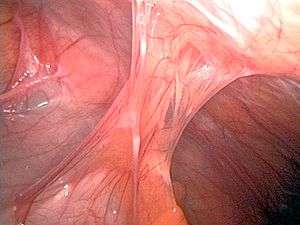

Adhesions after appendectomy | |

Adhesions are fibrous bands[1] that form between tissues and organs, often as a result of injury during surgery. They may be thought of as internal scar tissue that connects tissues not normally connected.